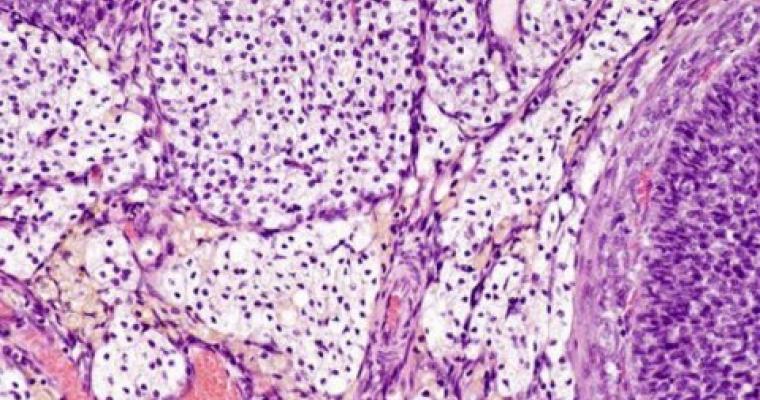

Come mai la Fascia è stata osservata proprio oggi?

La vera natura dell’interstizio è stata osservata per la prima volta grazie ad una nuova tecnica...